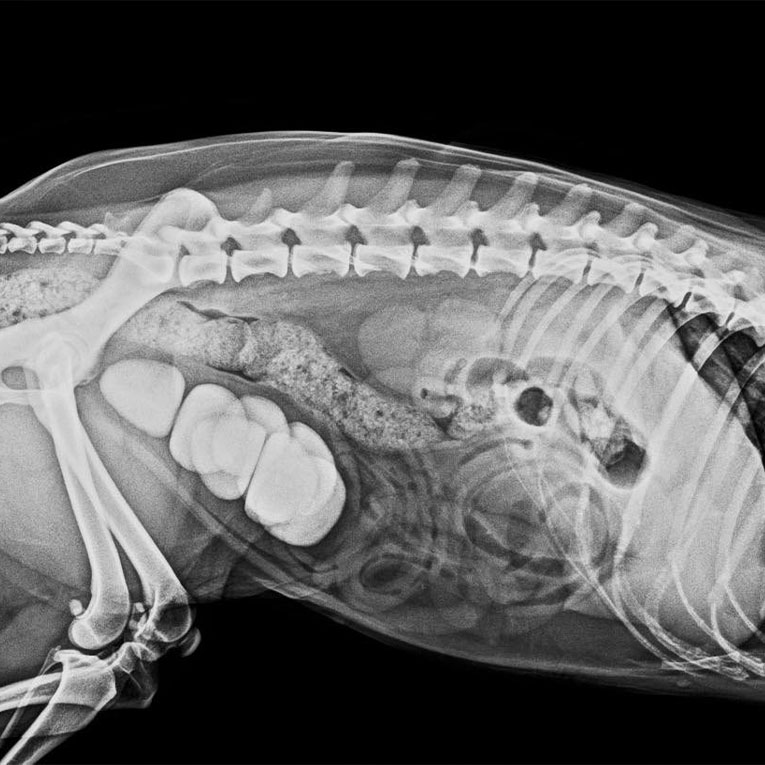

გულში არსებული პათოლოგიური ცვლილებების მიუხედავად, ჩაპას ესაჭიროებოდა სასწრაფო გადაუდებელი ქირურგიული ჩარევა ცისტოტომია, რადგან უროლითიაზის გამო შარდის ბუშტში არსებული სტრუვიტების ფონზე ის ვერ ახერხებდა ნორმალურად შარდვას და მუდმივად განიცდიდა ტკივილს.